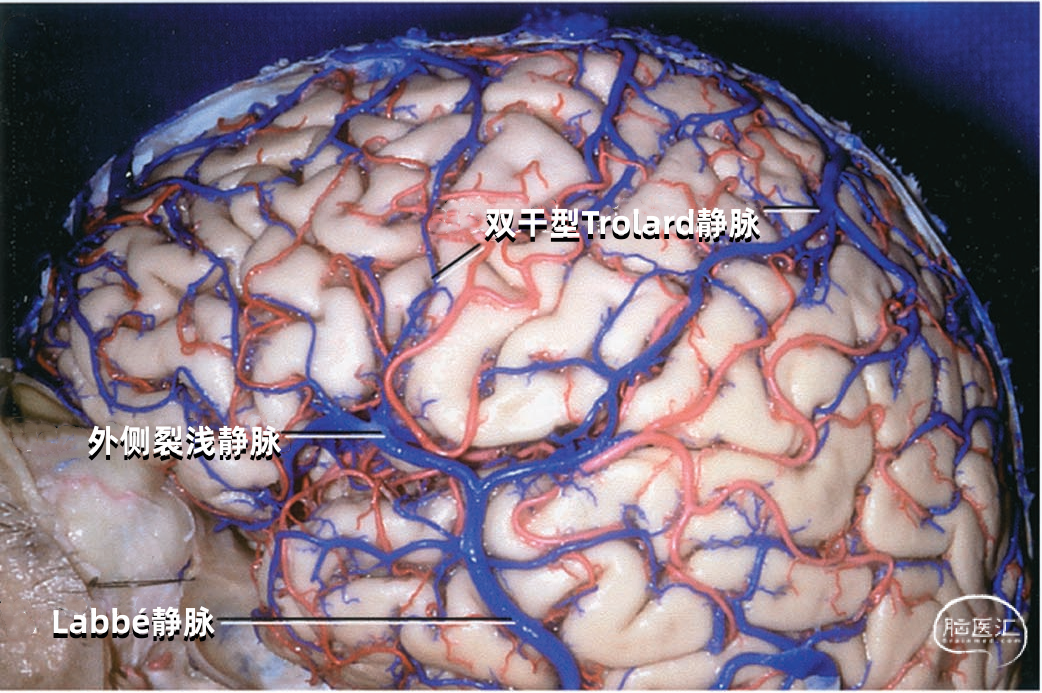

大脑外侧面最大的静脉是Trolard、Labbé、外侧裂浅静脉。 Trolard静脉是最粗大的吻合静脉,连接外侧裂静脉和上矢状窦。Labbé静脉则是连接外侧裂浅静脉和横窦的最粗大吻合静脉。外侧裂浅静脉沿外侧裂表面走行,而且主要沿蝶骨嵴汇入硬膜窦(蝶顶窦或海绵窦)。 虽然Trolard、Labbé静脉和外侧裂浅静脉大小可能相同,但更常见的是其中一支或两支血管比较粗大,而剩下的则细小甚至缺如。通常左右两侧血管的大小并不对称。

Trolard静脉又称上吻合静脉,是跨越额叶和顶叶,连接外侧裂与上矢状窦的最大吻合静脉。 在我们研究的20例半球标本中,发现15例Trolard静脉的位置相当于中央前静脉、中央沟静脉和中央后静脉,最常见的位置是中央后静脉水平。最靠前的Trolard静脉位于额前静脉水平,连接上矢状窦的前部和外侧裂浅静脉的前部。最靠后的Trolard静脉位于顶前静脉水平。 Trolard静脉通常以单干向前走行,汇入上矢状窦,与血流相反方向。通常Troland静脉在将要汇入上矢状窦前接受其他一些静脉的回流,它的下端通常以单一通道与外侧裂静脉相沟通,但也可在额叶和顶叶凸面的下部分成许多分支加入外侧裂浅静脉。有时会有两条同样大小的Trolard静脉连接外侧裂血管和上矢状窦之间。

下图示(左侧半球)外侧裂浅静脉与Labbé静脉之间有较大的吻合支。另外,有两支或双干型的Trolard静脉属支连接上矢状窦和外侧裂静脉,后方一支Trolard静脉在外侧裂浅静脉与Labbé静脉的结合处附近加入外侧裂浅静脉。

下图示(右侧半球)双干型的Trolard静脉连接于上矢状窦和外侧裂之间,一支越过额叶,另一支越过顶叶。外侧裂浅静脉与Labbé静脉之间也有一个粗大的吻合支。

下图示(右侧半球)没有明显的外侧裂浅静脉。有双干型Labbé静脉从外侧裂到横窦。中央沟静脉和额后静脉的大小几乎相同,组成双干型Trolard静脉,连接外侧裂和上矢状窦。中央沟静脉下部走行于中央沟内。

下图示双干型Trolard静脉和双干型Labbé静脉引流外侧裂附近的大部分静脉。